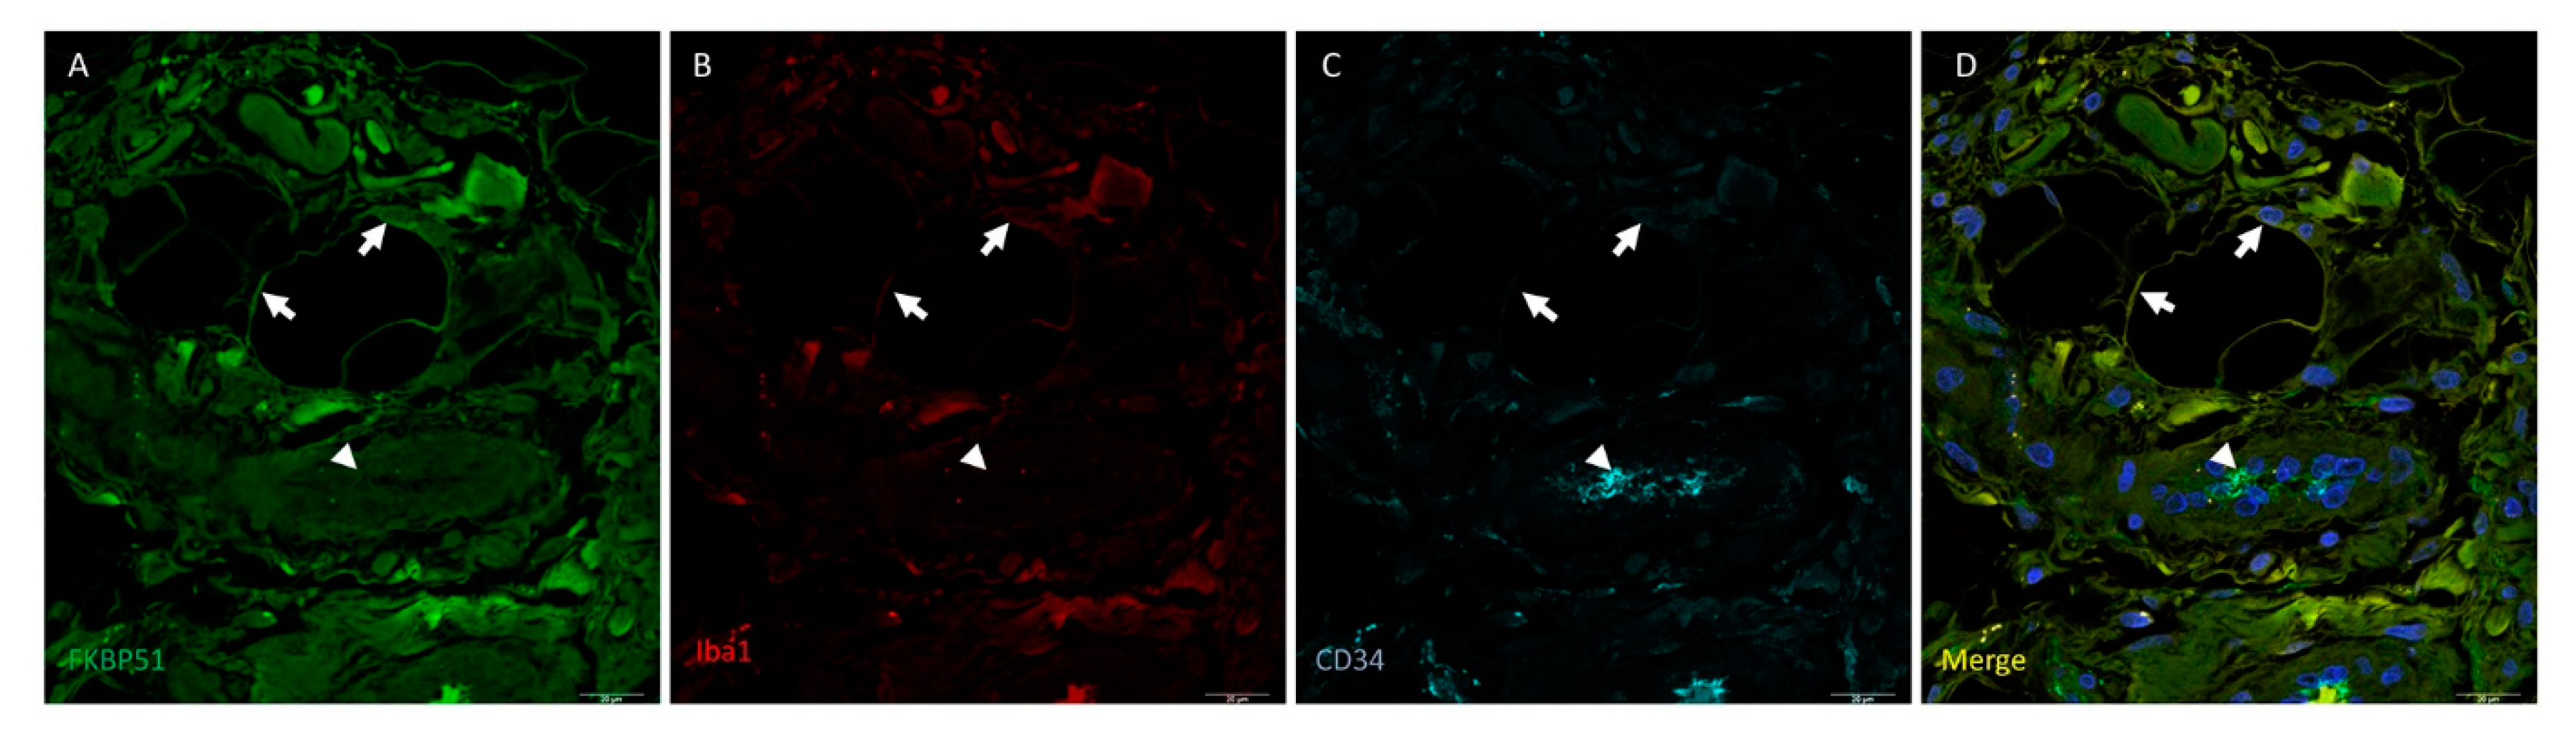

3. Results

4. Discussion